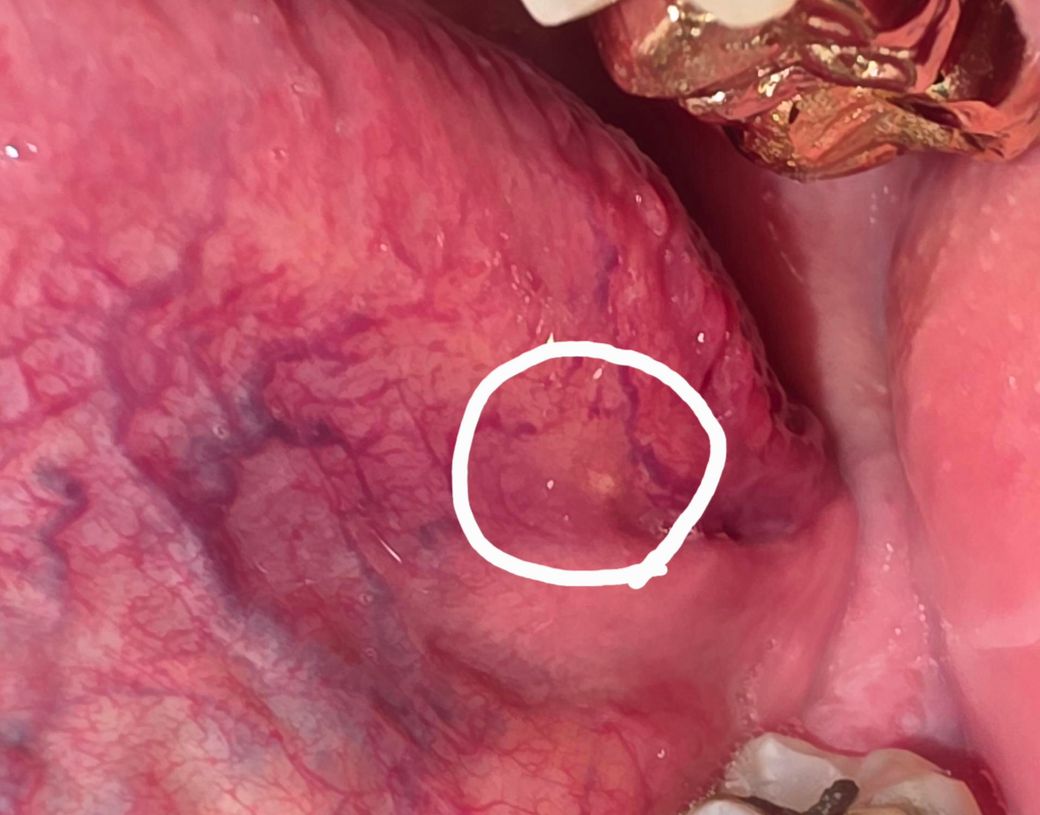

혀 엽상돌기 밑에 노란 돌기 같은 것이 생겼습니다.

엽상돌기 밑 부분에 노란색 돌기를 발견했습니다.

볼록 튀어나온 느낌보다는 정말 미세하게 표면이 올라와 있습니다.

사진 상 흰색 원 안의 부분입니다.

• 2번 째 사진

혀 아래부분엔 다양한 해부학적 구조가 있습니다 혈관, 지방샘, 림프샘, 근육, 신경 등이 지나가는데 그 중 지방샘으로 보입니다